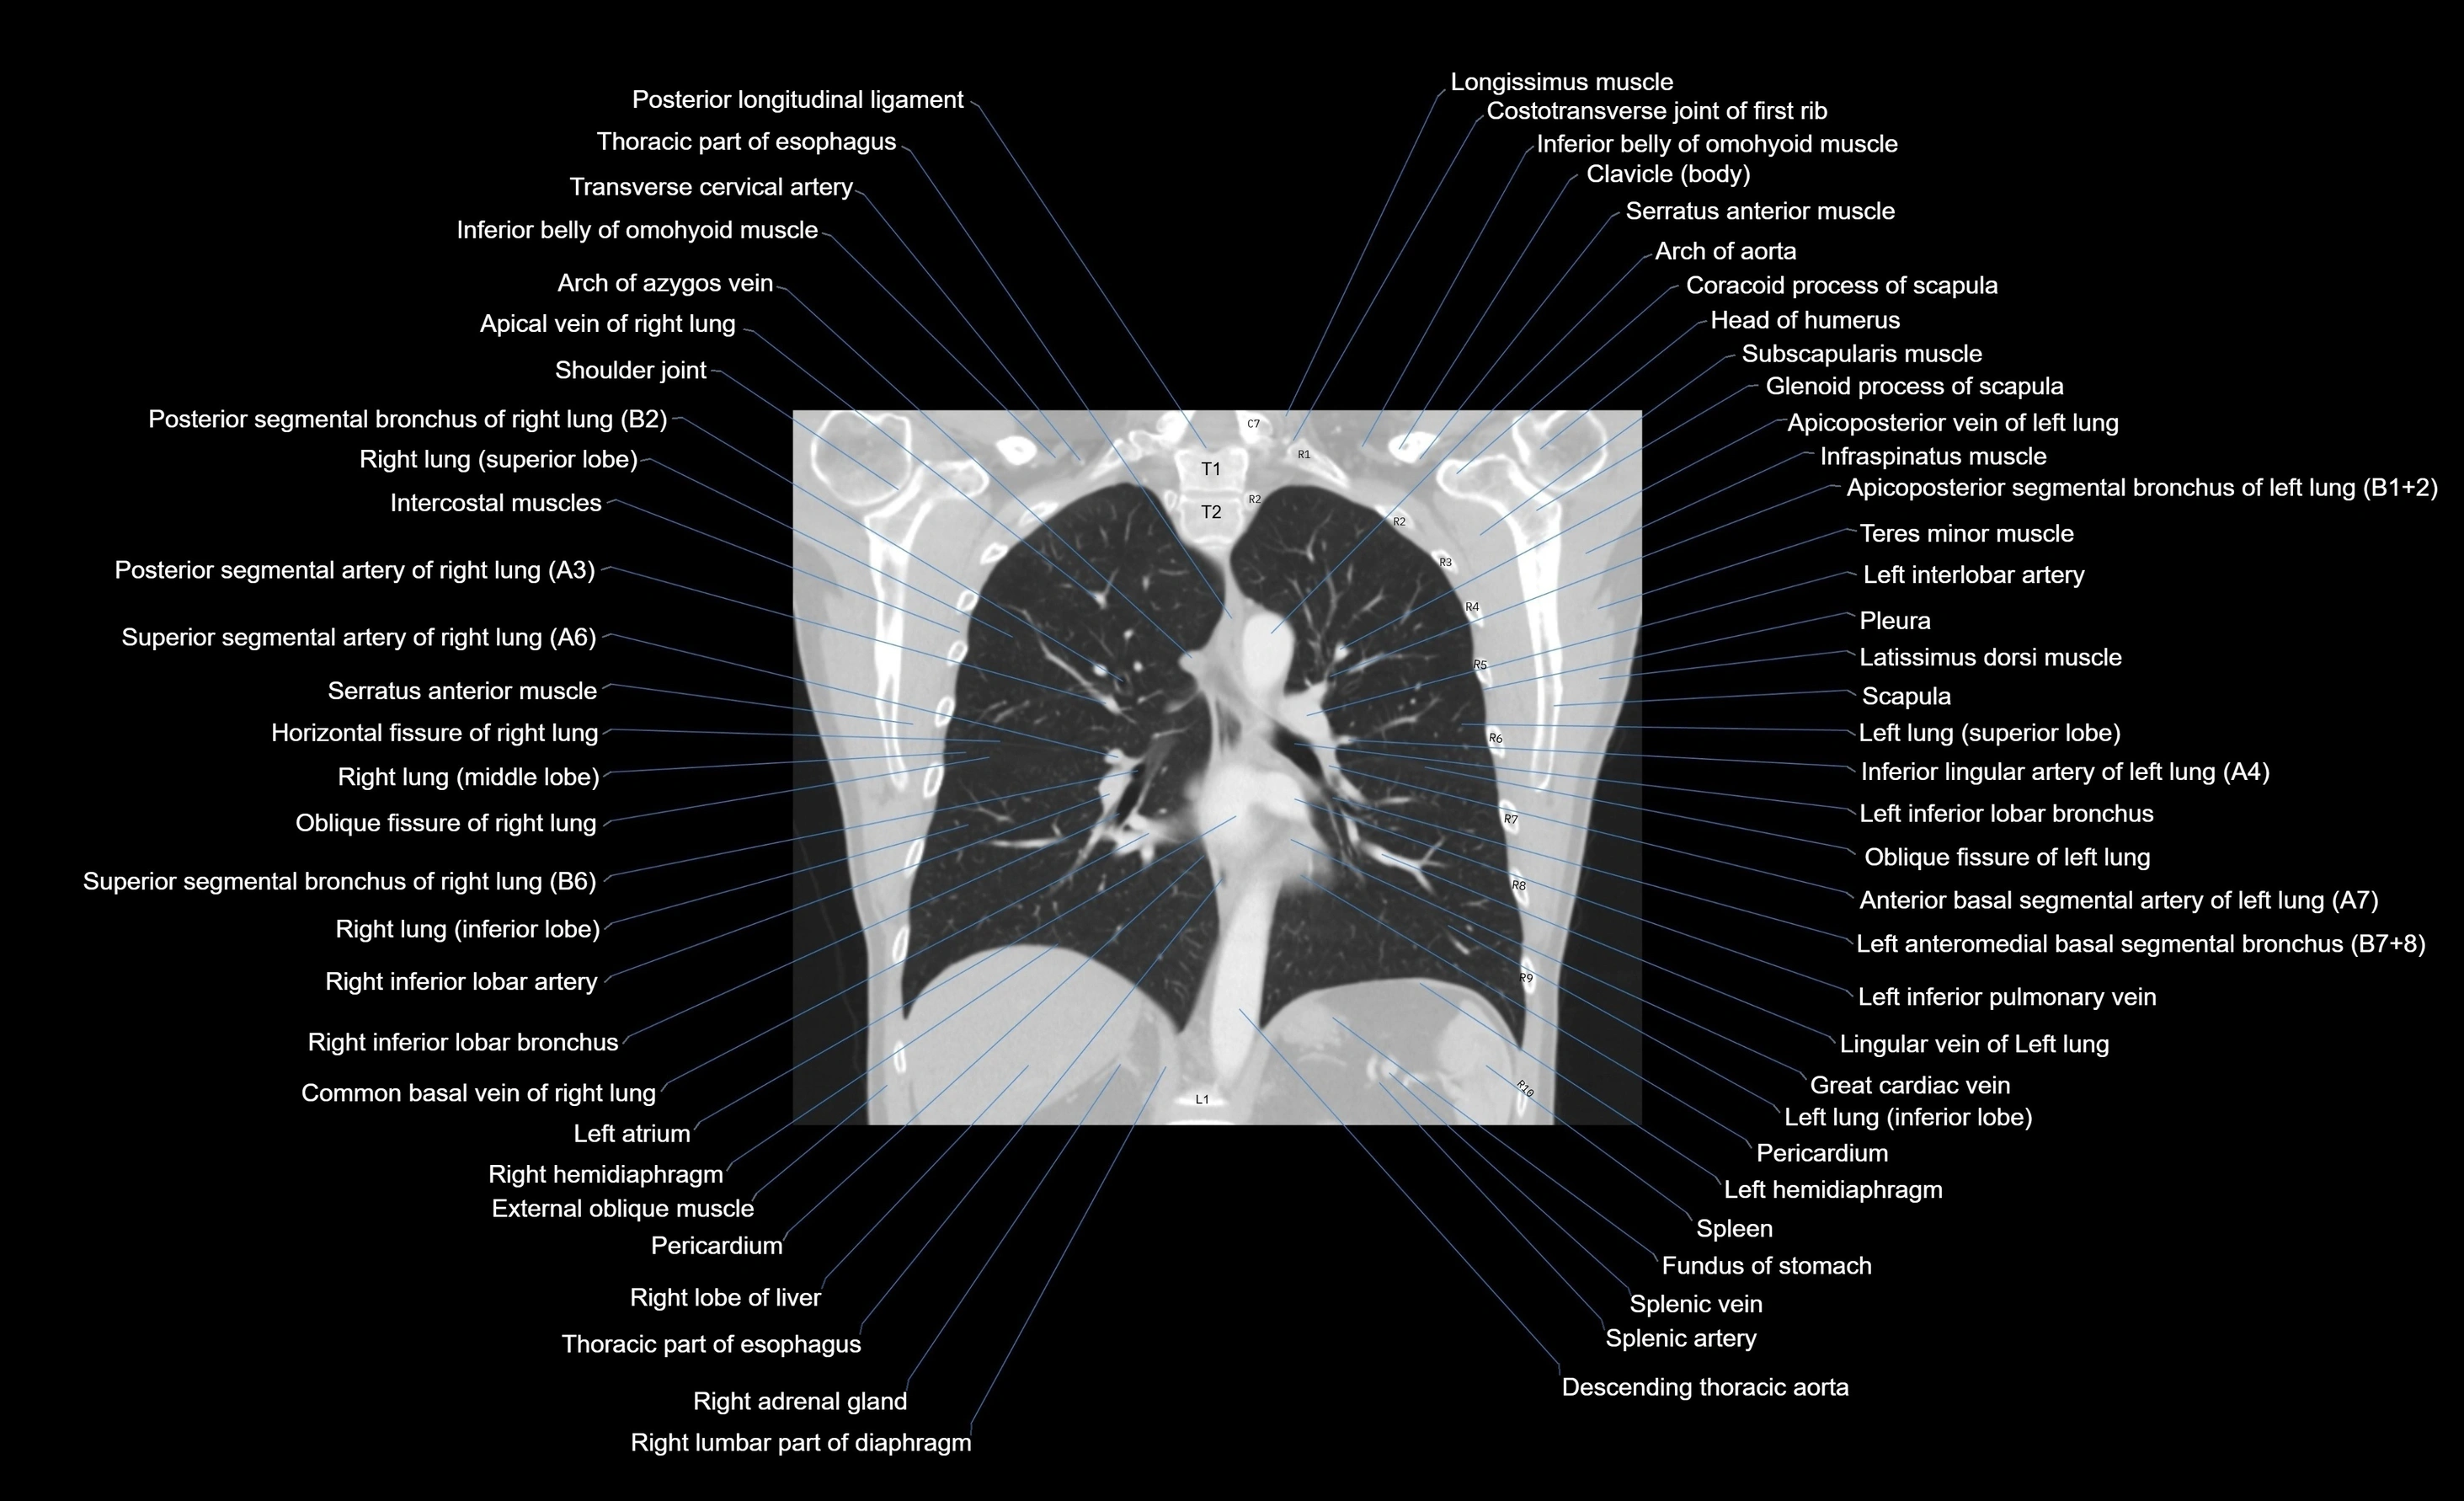

- T (Thoracic spine)